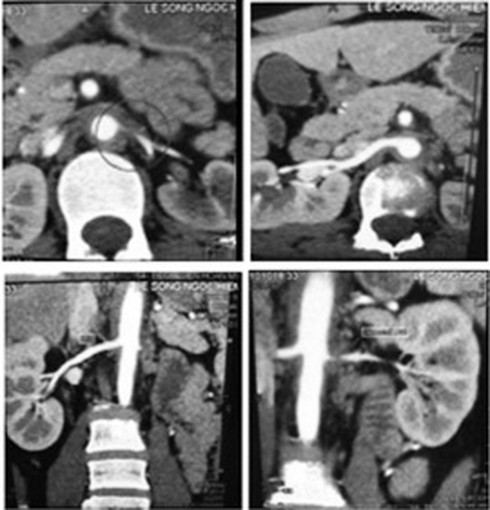

Hình ảnh phim chụp CT mạch máu của bệnh nhân Takayasu. |

Các xét nghiệm thường thể hiện tình trạng viêm nhưng không đặc hiệu. Phương pháp thăm dò hình ảnh như: chụp cộng hưởng từ, chụp cắt lớp vi tính và chụp mạch máu có bơm thuốc cản quang rất có giá trị chẩn đoán vị trí tổn thương.